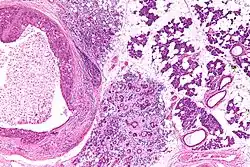

| Low magnification micrograph of a salivary duct carcinoma with characteristic comedonecrosis (left of image) adjacent to normal parotid gland (right of image). H&E stain. | |